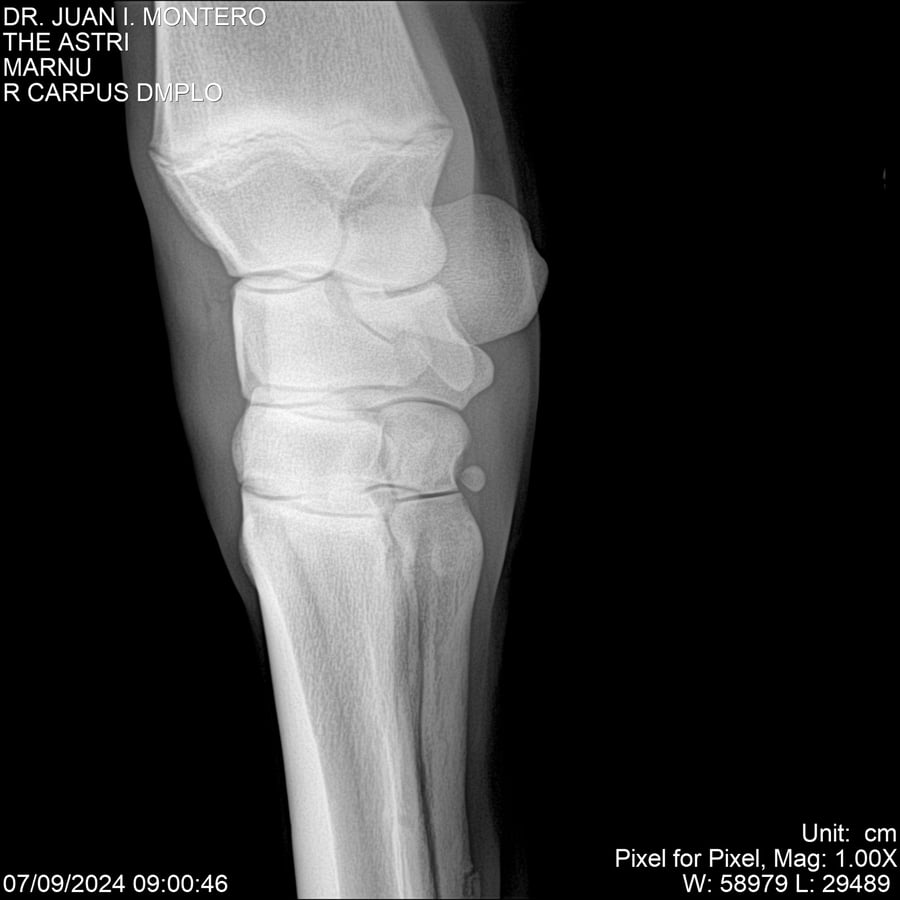

LOTE 10, THE ASTRI Lote Anterior Volver al remate Lote Siguiente Ficha Contacto Montevideo - Ficha del Lote Identificador: #282514 Categoría: Yeguarizos Montevideo - 60 Visualizaciones ClicData Contacto Empresa: Abelenda N. R., Walter Hugo Nombre*: Teléfono* : E-mail* : Mensaje Enviar Registrese gratis Este contenido Exclusivo está disponible sólo para usuarios registrados Ingresar